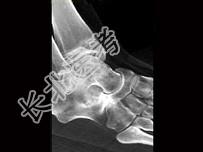

- 单项选择题患者足痛,如图所示, 最可能诊断为 ( )

A、缺血坏死

B、骨折

C、退行性关节病

D、跗骨联合

E、以上都不是